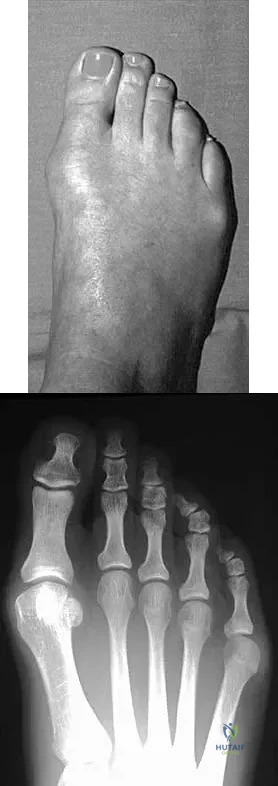

A 28-year-old woman has a moderate hallux valgus deformity and a prominence of the medial eminence. She can participate in all activities and reports that she could wear 3-inch heels in the past, but she now notes medial eminence pain even while wearing a soft leather flat shoe with a cushioned sole. She requests recommendations regarding surgical correction. Examination reveals a 1-2 intermetatarsal angle of 10 degrees. A clinical photograph and radiograph are shown in Figures 13a and 13b. What is the best course of action?

Explanation